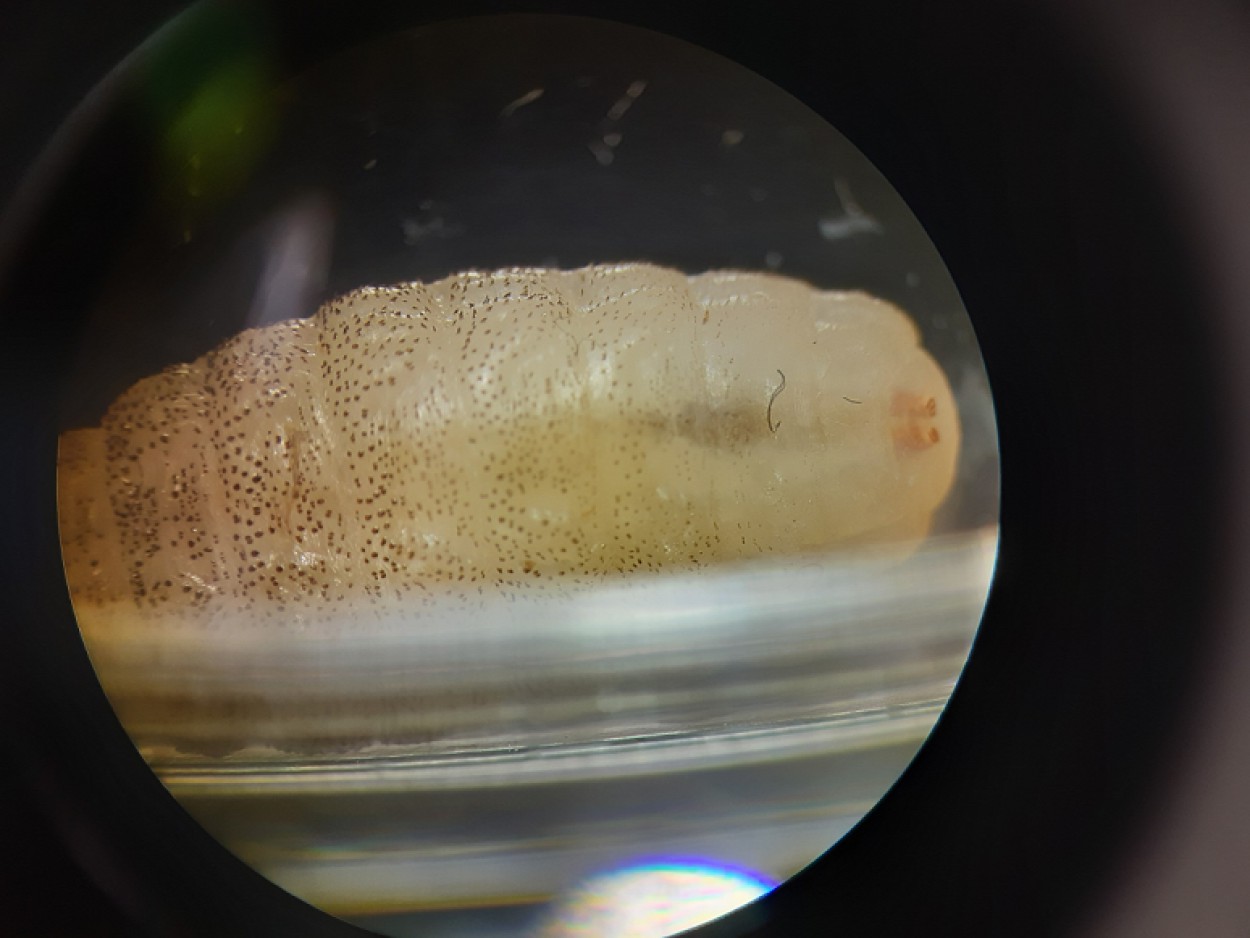

2 paveikslas Taip atrodo Cordylobia anthropophaga musės lėliukė. Ji susiformavo maždaug po 48 valandų nuo lervos identifikavimo. Kadangi ši musė vystosi pilnos metamorfozės ciklu, iš šios lėliukės po tam tikro laiko turėtų išsiristi suaugusi musė. Tačiau šiuo atveju iš jos musė neišsiris, nes lėliukė paskandinta 5 proc. formalino tirpale.